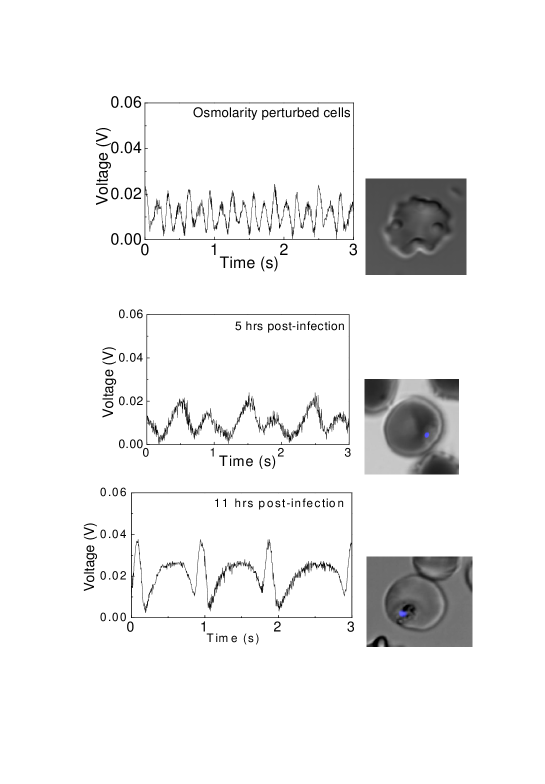

We have carried out measurements on two types of shape-distorted RBCs: those whose shapes are distorted simply by changing their osmolarity, and those whose shapes become distorted because of the malarial parasite within them. As already noted, there are two types of anisotropies: those which is related to shape changes - they give rise to form birefringence - and those which are induced by biochemical alterations within the cell - these give rise to intrinsic birefringence. In case of osmolarity-induced shape-distorted RBCs, the resulting form birefringence induces the cell to rotate within our trap. Fig. 3 shows results of measurements carried out on such cells. Also shown are results of rotations caused by the intrinsic birefringence of malaria-infected cells. In the former case we made measurements on cells using osmolarities ranging from 150 oSm to 1200 oSm; the rotational behavior did not change with change in osmolarity, with the peak-to-peak photodiode voltage remaining at 20 mV. The angle of rotation measured for 20 mV change in photodiode voltage corresponds 60 which when put in the equation hecht

(where n is the refractive index change) yields a value of n to be 1.210-2 for and wavelength =1064 nm. In contrast, malaria-infected cells yielded a photodiode voltage that depended on the stage of infection. We made measurements with a synchronous culture of the malarial parasite at fixed time points. Data obtained after 5 hours and 11 hours of infection is presented in Fig. 3 and clearly shows that the photodiode voltage increases as the malarial stage progresses, indicating stage-dependent change in the infected RBC’s intrinsic birefringence. In the early stages of infection (5h) the peak-to-peak voltage is 20 mV; this doubles 11h post infection, with the corresponding n change of 1.910-2. Twenty hours post infection n becomes 310-2. These values are consistent with the one previous microscopy report on malaria-infected RBCs suresh .

It is noteworthy that there is a difference in the rotation observed in osmolarity-perturbed cells and those that are malaria-infected. In former, the periodic rotations are symmetric whereas for malaria-infected cells they are distinctly asymmetric. Also, within a single cycle of rotation, there is marked asymmetry in the voltage value; this indicates that there is an inherent ellipticity in both infected and osmolarity-altered cells.